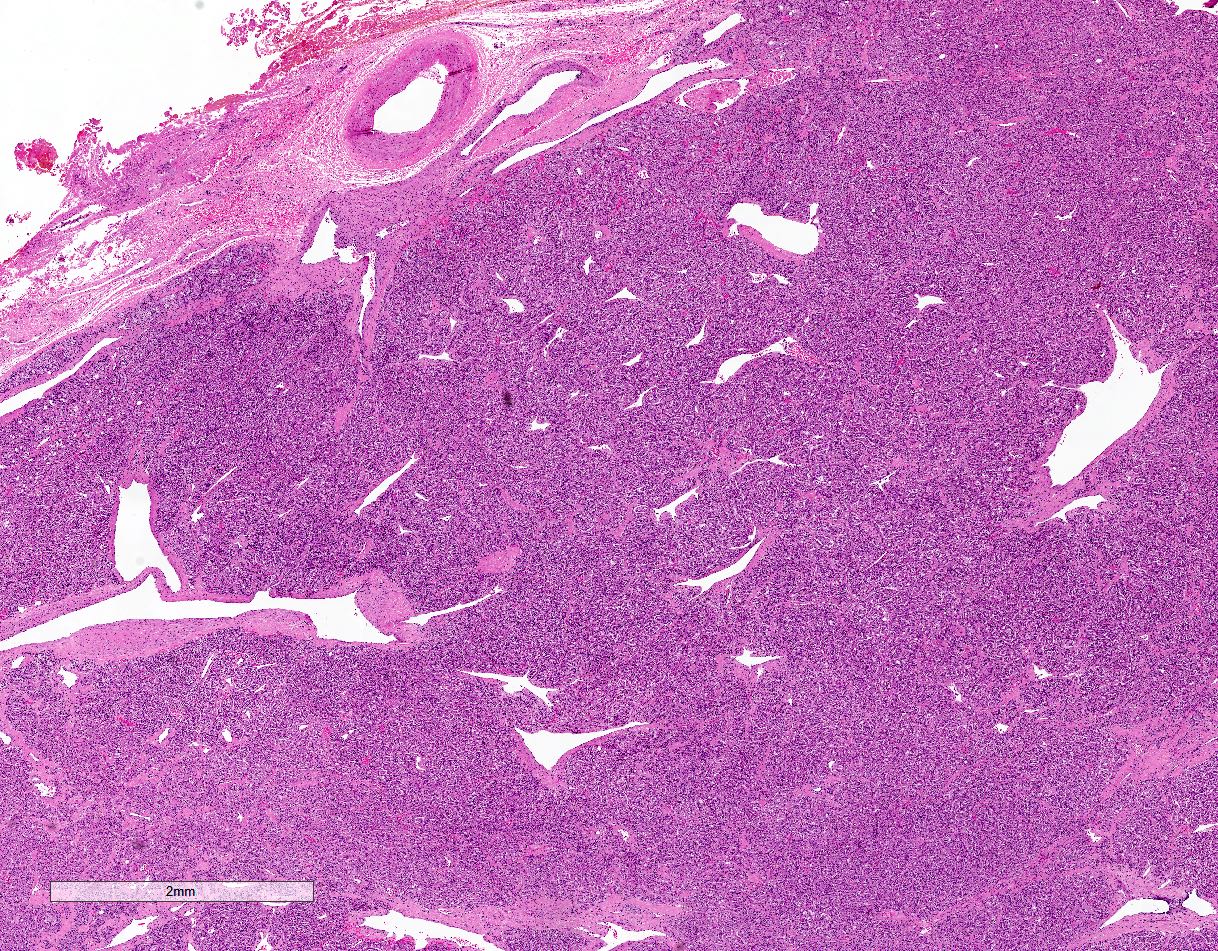

Microscopic (histologic) description

- Prevailing histologic pattern: epithelioid chief cells arranged in distinctive clusters / nests (zellballen pattern), separated by prominent fibrovascular stroma (J Clin Med 2018;7:280)

- Trabecular pattern: ribbons or cords of epithelioid cells divided by fibrous bands

- Other patterns: pseudorosette, angioma-like, spindled and sclerosing

- May have dysmorphic vessels, melanin-like pigment (neuromelanin) (pigmented paraganglioma), amyloid, abundant stroma and osseous metaplasia (Diagn Pathol 2012;7:77, Hum Pathol 1992;23:33)

- May have focal chronic inflammatory infiltrate

Microscopic (histologic) images

Contributed by Luvy Delfin, M.D. and Sylvia L. Asa, M.D., Ph.D.